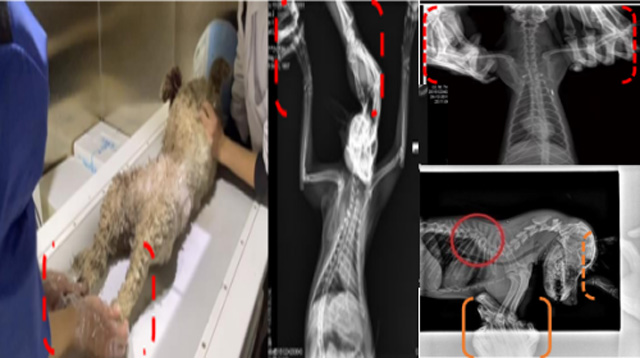

現(xiàn)在寵物醫(yī)療設(shè)備得到高速發(fā)展,現(xiàn)在有越來越多的寵物診療機構(gòu)配置X射線裝置如寵物DR。寵物骨折或者有其他疾病不能通過直觀看出來的。寵物診所醫(yī)生都會使用寵物DR來做輔助檢查。但是有時候?qū)櫸镝t(yī)生沒有加強防護,就在寵物DR室給寵物拍X片做檢查。這樣也是會受到X射線的輻射。因為X射線上崗是屬于職業(yè)病危害崗位。長期的輻射會對人體造成一定的危害。寵物醫(yī)生也需要接受X射線照射的上崗前都必須進行放射工作人員的職業(yè)健康體檢。體檢不合格的話是不能擔(dān)任放射工作的。未經(jīng)上崗前職業(yè)健康體檢的勞動者從事接觸職業(yè)病危害作業(yè)的行為,已經(jīng)違反了《中華人民共和國職業(yè)病防治法》第三十五條規(guī)定,依據(jù)《中華人民共和國職業(yè)病防治法》第七十五條規(guī)定,需要進行整改罰款。開展寵物放射診療活動,在日常工作中,對本機構(gòu)的X射線危害的職業(yè)病防治,需要知道并做到以下內(nèi)容:

建造X射線機房時尋找專業(yè)防護施工隊伍,對機房四方及上下方墻體進行屏蔽防護,盡可能隔室操作,使用鉛防護門并安裝工作指示燈張貼警示標(biāo)識進行提醒。放射工作人員跟寵物主進入DR室需要穿戴鉛衣、鉛帽、鉛手套等做好防護,減少X射線的輻射。避免暴露在照射范圍中。寵物醫(yī)生上崗前、在崗時、離開崗位時候的職業(yè)健康體檢。如果檢查異常就需要復(fù)查跟調(diào)離放射崗位。實施個人劑量監(jiān)測和防護知識培訓(xùn)。并在勞動合同中向放射工作人員告知X射線危害相關(guān)內(nèi)容。定期委托職業(yè)技術(shù)服務(wù)機構(gòu)對機房防護、放射診療設(shè)備性能進行檢測。不能忽略了對人的保護。